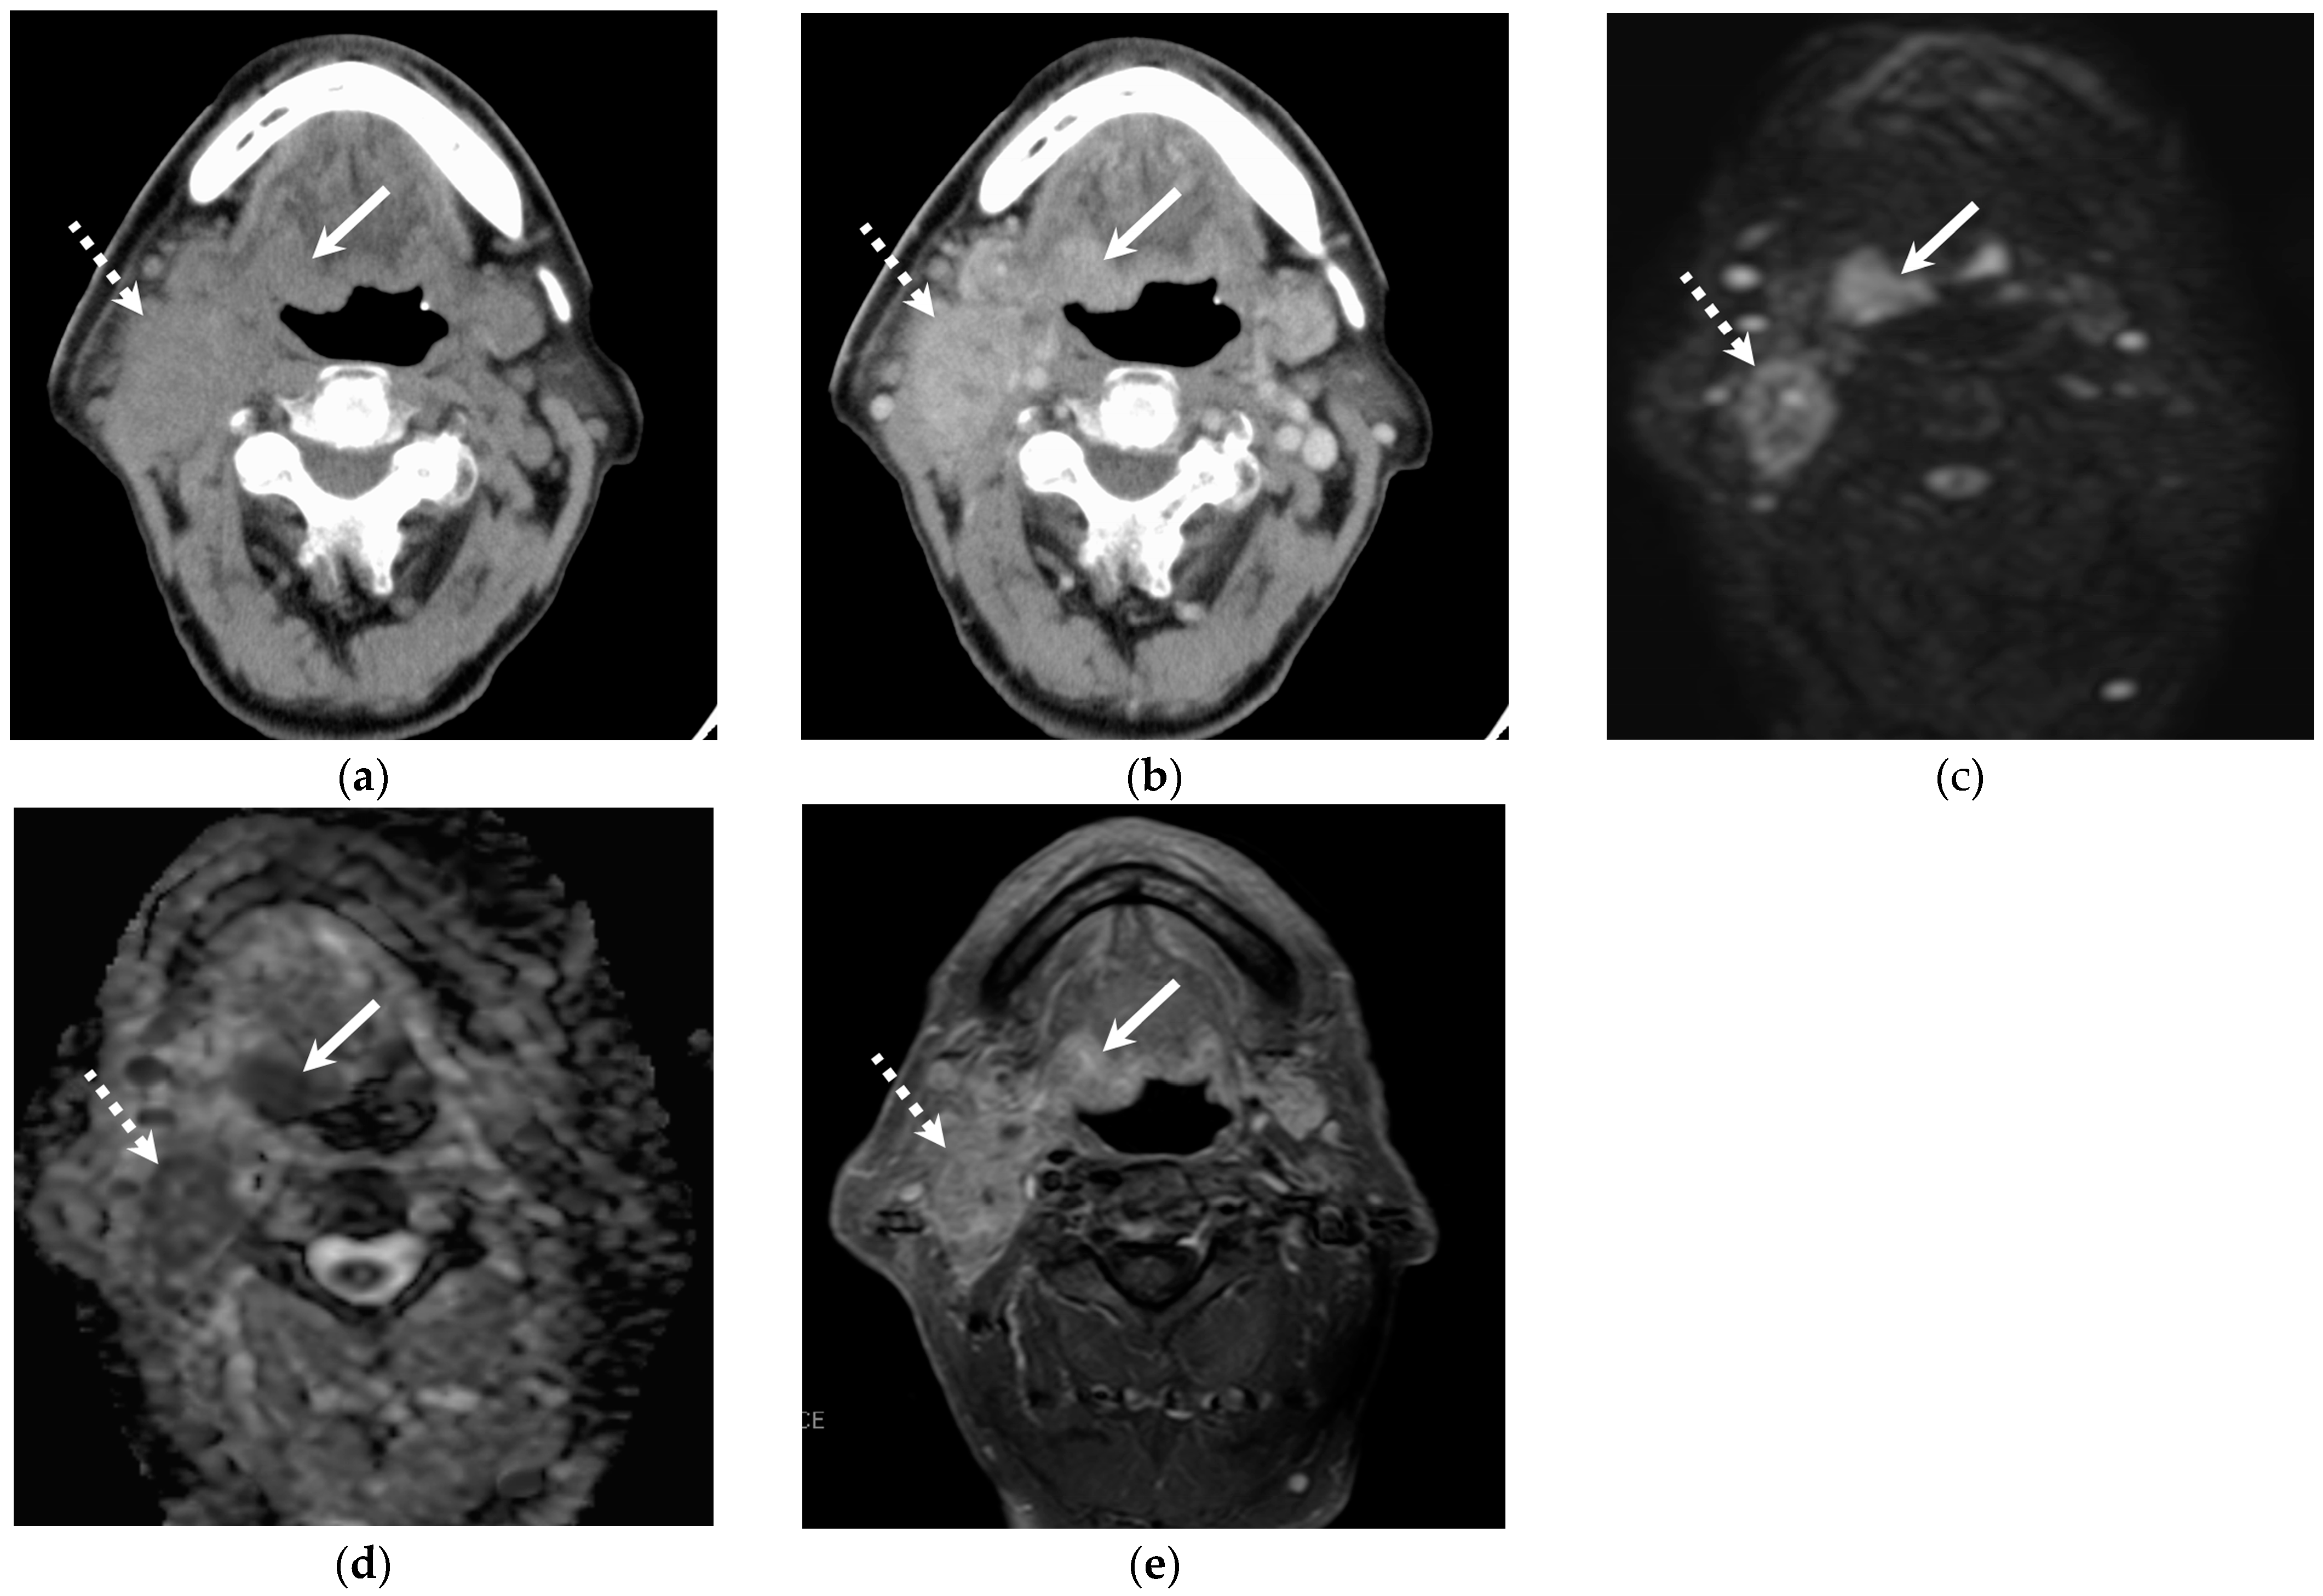

3.2. Quantitative and Qualitative Imaging Findings of the Primary Lesion

3.4. Qualitative Imaging Findings of Cervical Lymph Node Metastasis

4. Discussion